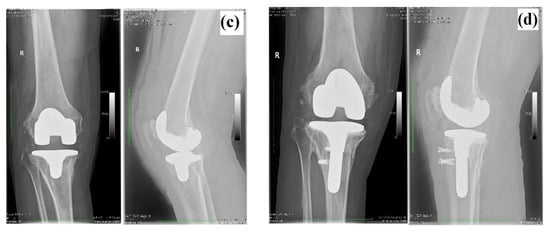

In Figure 2 are presented the photographic images of retrieved tibial components after 10 years, showing the surface deterioration especially on the surface of UHMWPE component (delamination, scratching), along with the accumulation of pelleted synovial fluid in the stem of tibial component (Figure 2b).

Figure 2.

Photographic images of retrieved tibial components of knee prosthesis. (a) Assembled tibial components; (b) titanium component and synovial fluid collected from the stem (white arrow); (c) separate metallic and ultra-high-molecular-weight polyethylene (UHMWPE) component, showing surface delamination (white arrow); (d) acrylic cement detached from the metallic component.